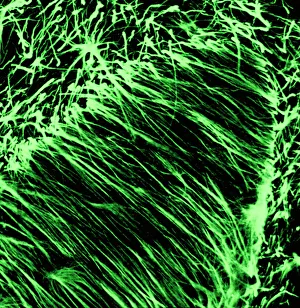

The central nervous system, the intricate network that governs our every thought and movement, is a marvel of complexity. From the delicate cerebellum tissue to the detailed light micrograph capturing its essence, we are reminded of its importance in maintaining balance and coordination. Anatomy comes alive as we explore the human brain from an inferior view. The intricacy of brain fibers is revealed through DTI MRI scans like C017/7099 and C017/7035, showcasing their vital role in transmitting information throughout this extraordinary organ. Artistic renderings bring us closer to understanding the medulla oblongata's significance within the brain. Its portrayal in various artworks allows us to appreciate how it controls essential functions such as breathing and heart rate. As we delve deeper into studying the central nervous system, models of the human brain provide invaluable insights into its structure and organization. Lateral views reveal countless regions responsible for cognition, emotion regulation, sensory perception, and motor control. Microscope slides offer glimpses into nerve cells' intricate architecture—a testament to their ability to transmit electrical signals at lightning speed. Meanwhile, glial stem cell cultures captured under a light microscope remind us of their crucial role in supporting neuronal function. Finally, artistic representations unveil the limbic system's enigmatic nature—an interconnected web responsible for emotions and memory formation. These captivating artworks allow us to visualize this complex network within our brains. Exploring these hints provides a glimpse into the awe-inspiring world of our central nervous system—the very foundation upon which our thoughts, actions, memories reside—reminding us just how remarkable our brains truly are.